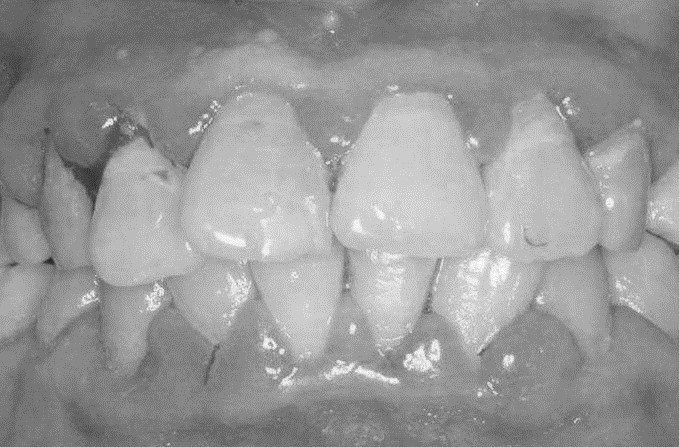

患者,女,52歲。因刷牙出血前來就診。自述刷牙時(shí)牙齦出血2年余,有時(shí)吃蘋果,饅頭等食物時(shí)牙齦出血,近1個(gè)月早晨起床偶有唾液中帶紅色血絲。曾作常規(guī)血象檢查,未見異常。無咬合不適或牙齒松動(dòng)。檢查可見全口牙石(+),有大量菌斑堆積,全口牙齦齦緣中度充血,齦乳頭充血腫大,探診出血明顯,但無附著水平喪失,牙齒無松動(dòng),咬合關(guān)系未見異常。X線片顯示全口牙槽骨無明顯吸收。檢查結(jié)果如下圖: